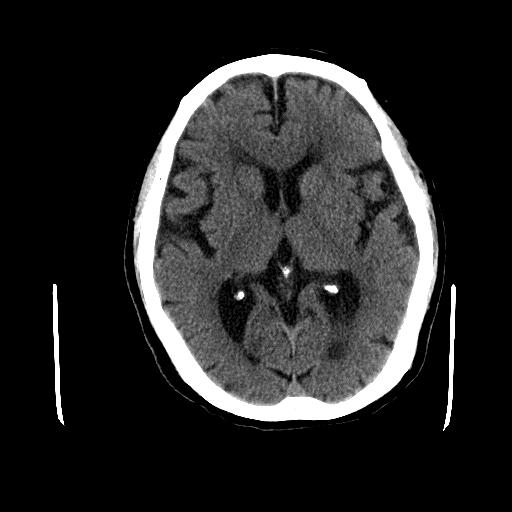

接诊患者后,神经内科最重要的就是查体,当时就发现患者面部无表情,呈面具样,伸舌居中,查到右侧肢体时感觉肌张力明显升高,握拳还是有力的,也可以抬离床面,但是双侧痛觉是对称的,双下肢病理征也是阴性。当时给我的第一印象不像是中风了。后面就给患者完善了头颅CT及血生化检查,测生命体征血糖、血压都在正常范围内,心电图也是正常的。任何一个疾病的发生绝不是偶然,肯定有一些诱发因素。所以当时综合以上的依据脑梗死诊断依据不充分,到像是一个帕金森综合征,当时因为考虑疾病病程短,又没有明显震颤,所以就向患者和家属交代了病情。

帕金森病一般起病缓慢,早期很难识别出来。该患者起病时便没有震颤,主要表现为运动迟缓,肌张力高,并且起病时间短,很容易被误诊为脑梗死,但是该患者无高血压、糖尿病、高血脂等危险因素,家族中也没有脑卒中发病史,头颅CT也没有看到梗死灶,缺乏充足的证据诊断为脑梗死。其次脑梗死一般都会有神经系统的定位体征,所谓临床三偏,偏瘫、偏盲、偏身感觉障碍,患者缺乏符合脑梗死诊断的神经系统定位体征。患者在前期诊断未进入综合医院的神经内科专科就诊,而一直以为脑梗死在基层医院治疗,症状没有明显改善而没有进一步寻找依据,这种情况误诊在临床中还是经常可以见到的。